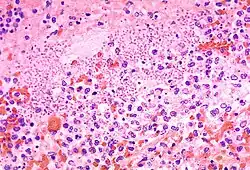

L'aspetto clinico più caratteristico della malattia è l'ingrossamento di uno o più linfonodi, prossimi al luogo delle punture della pulce (che è più frequentemente la zona inguinale e quella ascellare). Il linfonodo infiammato viene denominato bubbone, ovvero un rigonfiamento edematoso il cui interno evolve formando un accumulo emorragico e necrotico. Ciò è la conseguenza del fatto che il batterio Y. pestis continua a sopravvivere anche dopo essere stato fagocitato dai leucociti e si accumula all'interno del linfonodo, riproducendosi e producendo tossine beta-bloccanti e in grado di bloccare alcune risposte immunitarie.[63]

La maggioranza dei pazienti presenta un solo bubbone. Il 70% dei pazienti presenta un linfonodo ingrossato in area inguinale, nei restanti casi la sede è il collo o la nuca, o la catena di linfonodi ascellari, o la regione femorale. I bubboni generalmente non sono appariscenti: possono avere qualsiasi dimensione compresa tra 1 e 10 centimetri, la loro localizzazione è profonda, sono soffici al tatto e dolorosi. Spesso sono visibili solo con una indagine ecografica, o una piccola area di cute eritematosa può essere unico indizio della loro presenza. Se i bubboni sono duri e tesi è indizio che sono superinfetti, e in alcuni casi si possono trattare come ascessi, applicando però rigorose misure di protezione. È anche possibile la formazione di bubboni nella regione mesenterica, causando dolore addominale.

Peste setticemica

È la setticemia sistemica derivante dalla propagazione di Y. pestis nell'apparato circolatorio che lo porta a raggiungere tutte le parti dell'organismo. Può seguire come seconda fase in conseguenza del cedimento di uno o più linfonodi quando questi, già trasformati in bubbone in un processo di infiammazione emorragica, non sono più in grado di contenere il batterio al loro interno. In questo quadro le tossine batteriche che circolano liberamente possono determinare sindromi da coagulazione intravascolare disseminata (CID) che colpiscono a partire dalle estremità, causando necrosi di dita o piedi, ecchimosi diffuse sull'intera superficie del corpo, e vengono esaurite le capacità coagulatorie del corpo causando emorragie negli organi interni. La CID costituisce un quadro estremamente pericoloso che deve essere trattato in modo aggressivo e tempestivamente, in caso contrario conduce alla morte nel corso di poche ore. Il quadro setticemico produce facilmente scompensi renali, cardiocircolatori e sindromi multi-organo.[4][61][62]